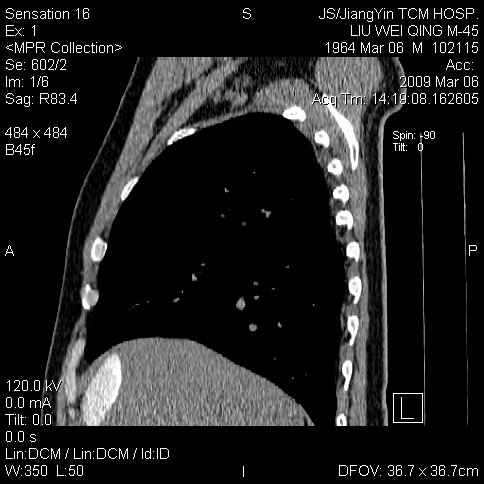

标题: CT18518:胸部扫描时发现肝边缘钙体影。请问是韧带钙化吗? [打印本页]

标题: CT18518:胸部扫描时发现肝边缘钙体影。请问是韧带钙化吗?

考虑肝内右外侧缘两处钙化,原因呢?(血管病变或其它)

考虑肝包膜下陈旧性包裹性积液。

考虑---局限性腹腔积液〔钙乳性〕。    一般多为炎症刺激造成局部钙乳沉着所致。

考虑肝包膜下钙化

考虑肝包膜下钙化.